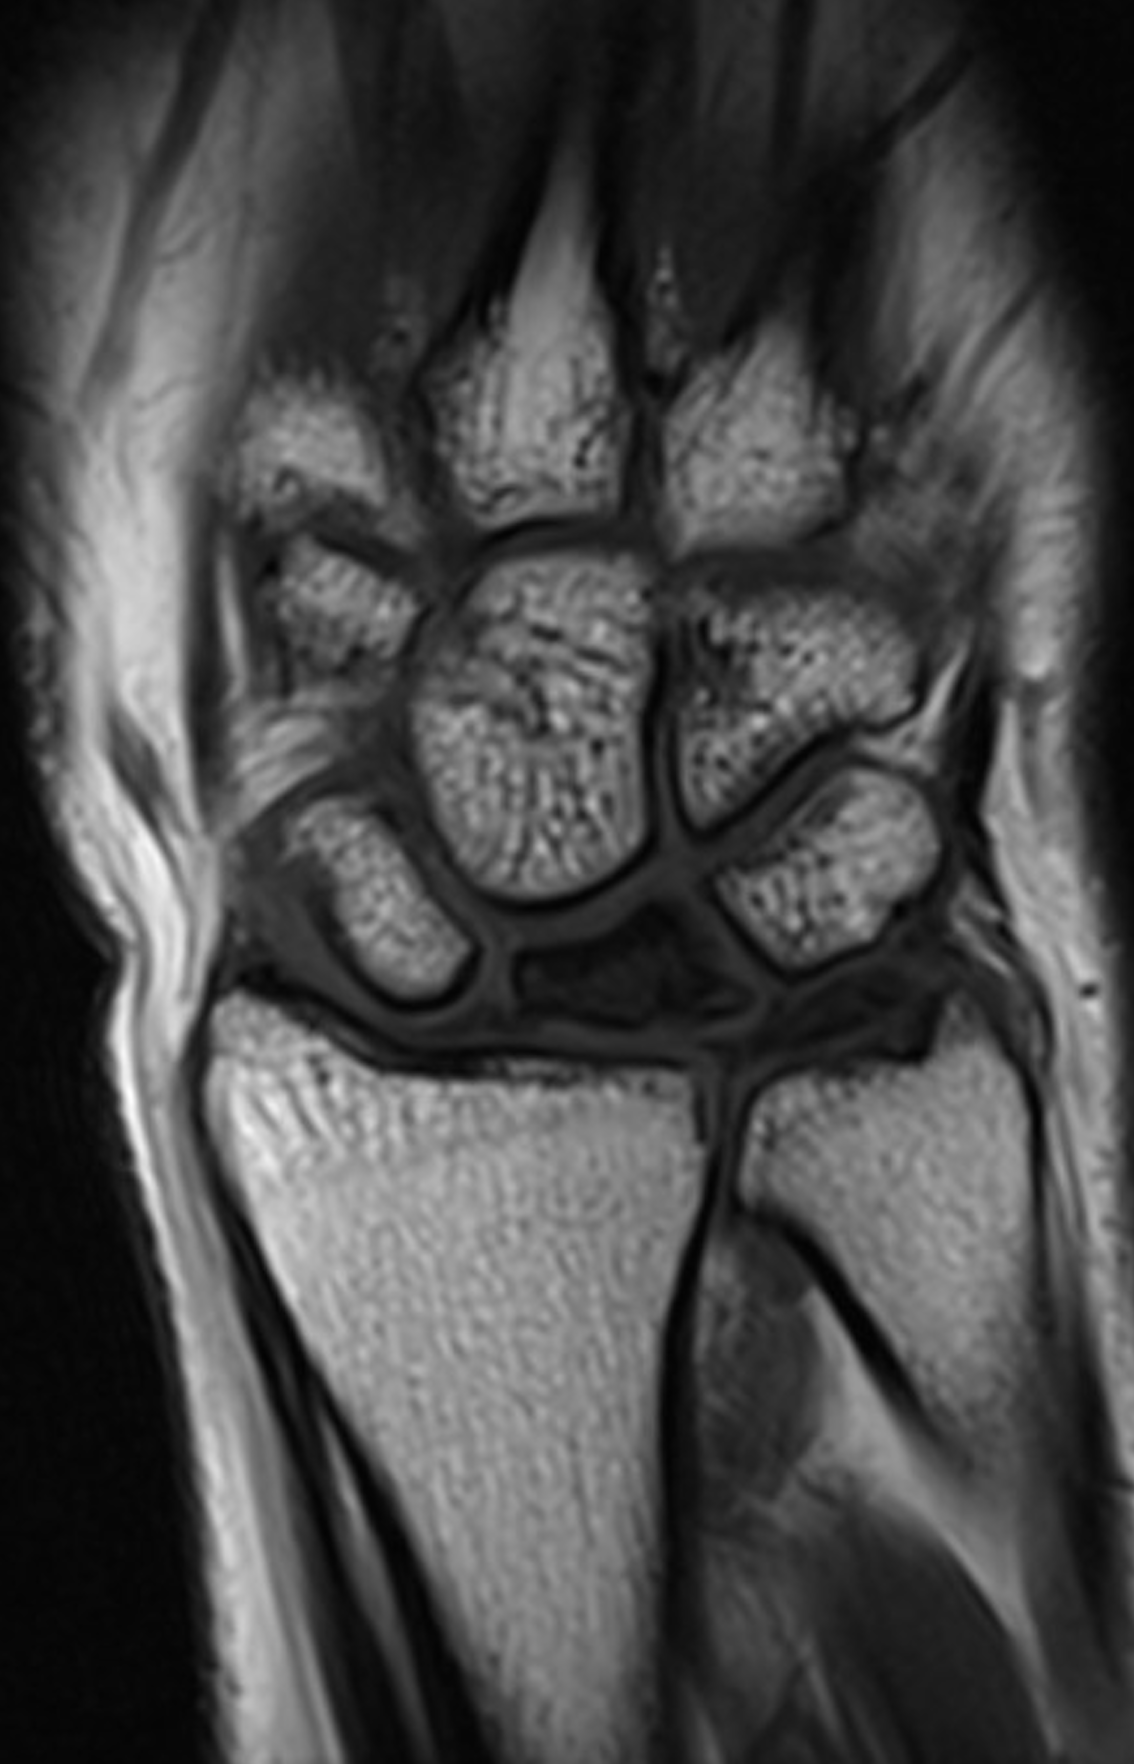

Patient A 21-year-old, right-dominant female was seen as an outpatient due to pain in her right wrist during hockey and sailing. There was no clear trauma of the wrist. The wrist was sometimes swollen during painful periods. During physical examination the wrist was not swollen, and the patient had pain upon pressure on the dorsal wrist and a painful Watson test, without click. Wrist pronation-supination was 80/0/80 (R) and 90/0/90 (L), dorsal-palmar flexion 30/0/30 (R) and 80/0/80 (L), ulnar and radial deviation 20/0/20 (R) and 30/0/30 (L). Grip strength was 20 kg (R) and 33 kg (L) (Jamar Dynamometer, Therapeutic Instruments, USA). X-ray of the right wrist showed height loss and some sclerosis of the lunate, suspicious for Kienböck’s disease Lichtman stage 2 (figure 1). The wrist X-ray also showed a neutral wrist, meaning equal length of the radius and ulna. MRI showed avascular necrosis of the lunate (figure 2).